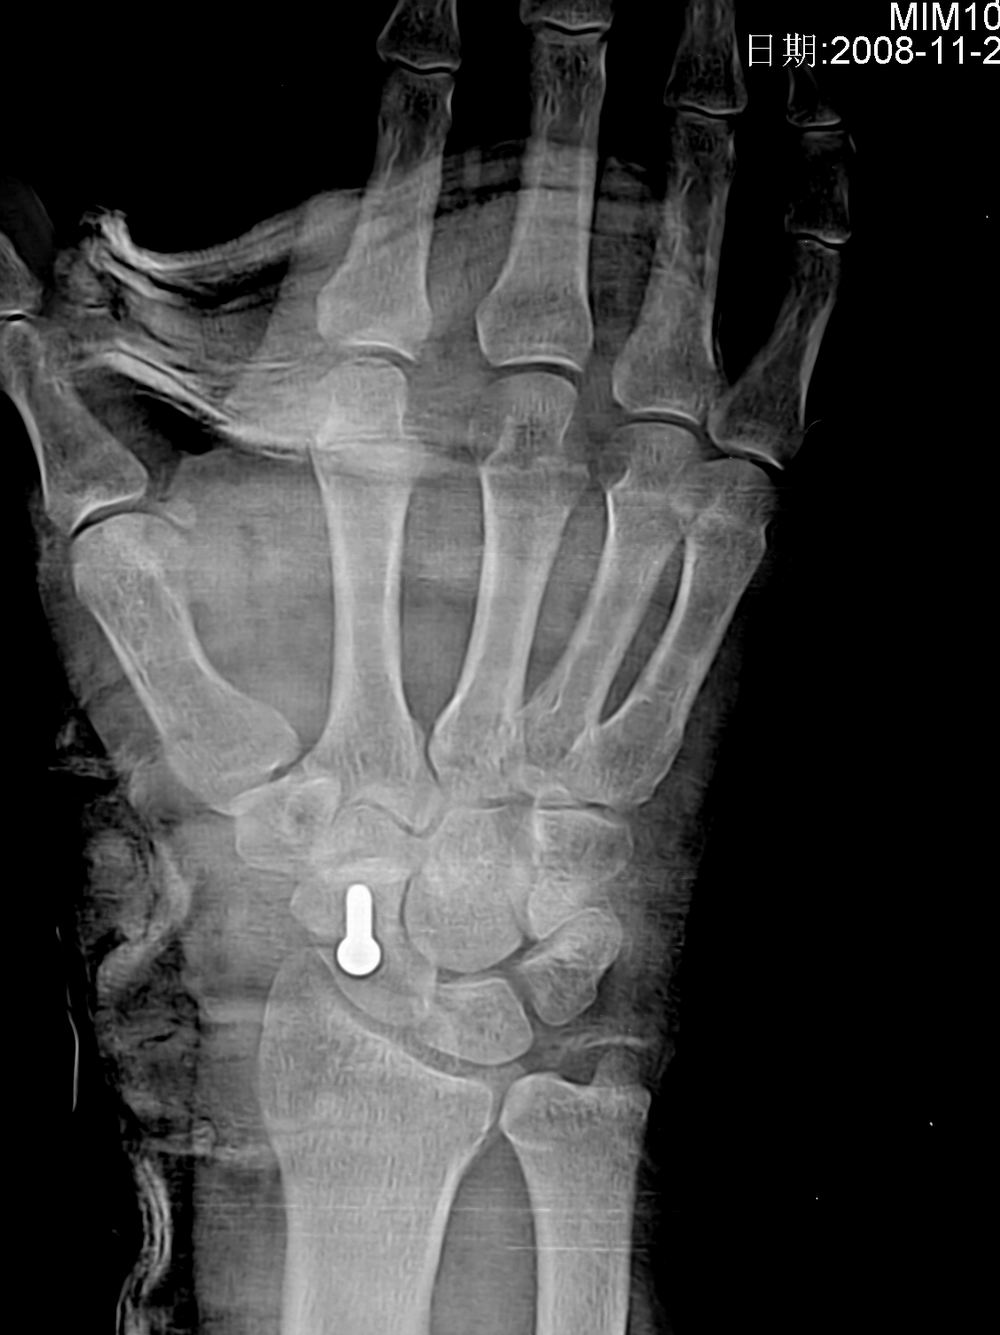

标题: X5107 :舟骨骨折

病人来的时候由于韧带砍断了,体位不正,在接韧带时发现舟骨有骨折,做了手术。

术后片如下: